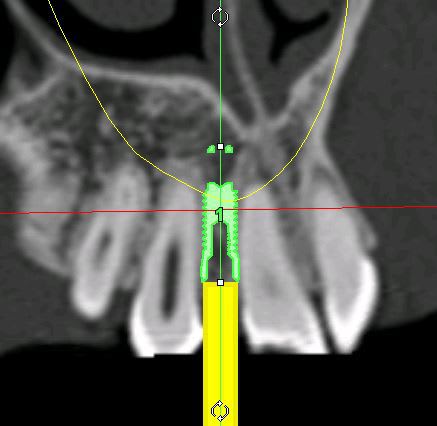

je mets les coupes et les radios post op...

intervention "quasi" flaless, juste des incisions crestales en W pour manager les papilles...

très honnêtement c'est bien mais je ne vois absolument pas pourquoi il faut guider l'instrument dans un cas comme ça, car pour la latéralité, tu suis les axes des autres dents, avec précautions ok mais bof, et pour l’épaisseur, c'est un boulevard

j'ai fais ça à main levée, et c'est tout simplement à la porté de tout praticien consciencieux, ce qui n'enlève rien au coté intéressant de ton outil.

c'est un boulevard en épaisseur, ok...

l'intérêt...c'est qu'en une petite heure c'était plié, provisoires inclues...et sans ouvrir grand pour contrôler les proximités radiculaires et faire radio sur radio de contrôle pour ne pas toucher aux racines...